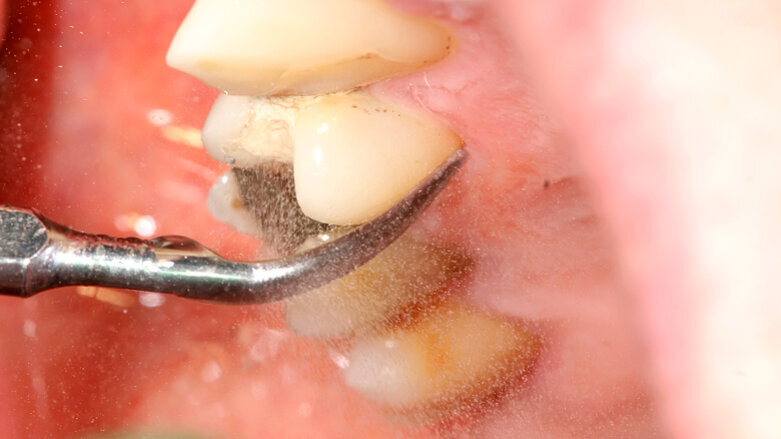

The study was carried out with 90 patients with Type 2 diabetes. Those randomly assigned to the treatment group received oral hygiene instructions and underwent scaling and root planing using ultrasound and Gracey curettes over six months. Those in the control group received oral hygiene instructions and underwent supragingival removal of plaque and calculus using ultrasound over the same period. During this time, the researchers assessed pocket depth, gingival and plaque indices, bacterial counts, and fasting plasma glucose and serum haemoglobin A1c (HbA1c) levels, the last of which are significantly increased in diabetics.

“The main conclusion of the study is that the non-surgical treatment of periodontitis improves the glycaemic status and levels of glycated haemoglobin, and therefore proves the great importance of oral health in these patients,” said Prof. José López López, medical director of the university’s dental clinic.